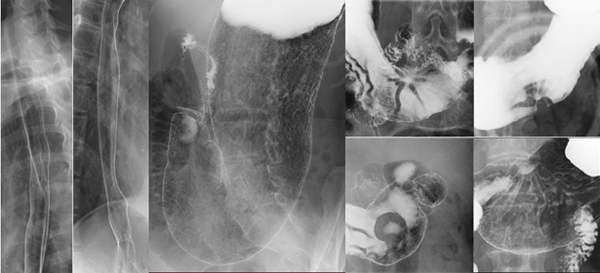

バリウムなどの造影剤を使用して体内臓器の形態、機能をリアルタイムに映像として観察することができます。

平面検出器(FPD:Flat Panel Detector)を搭載したX線TVを使用しているため、高画質で被ばくの少ない検査、治療が行えます。

バリウムと胃を膨らます炭酸の粉(発泡剤)を飲んでいただき、食道から胃・十二指腸までの上部消化管を透視で確認しながら撮影します。